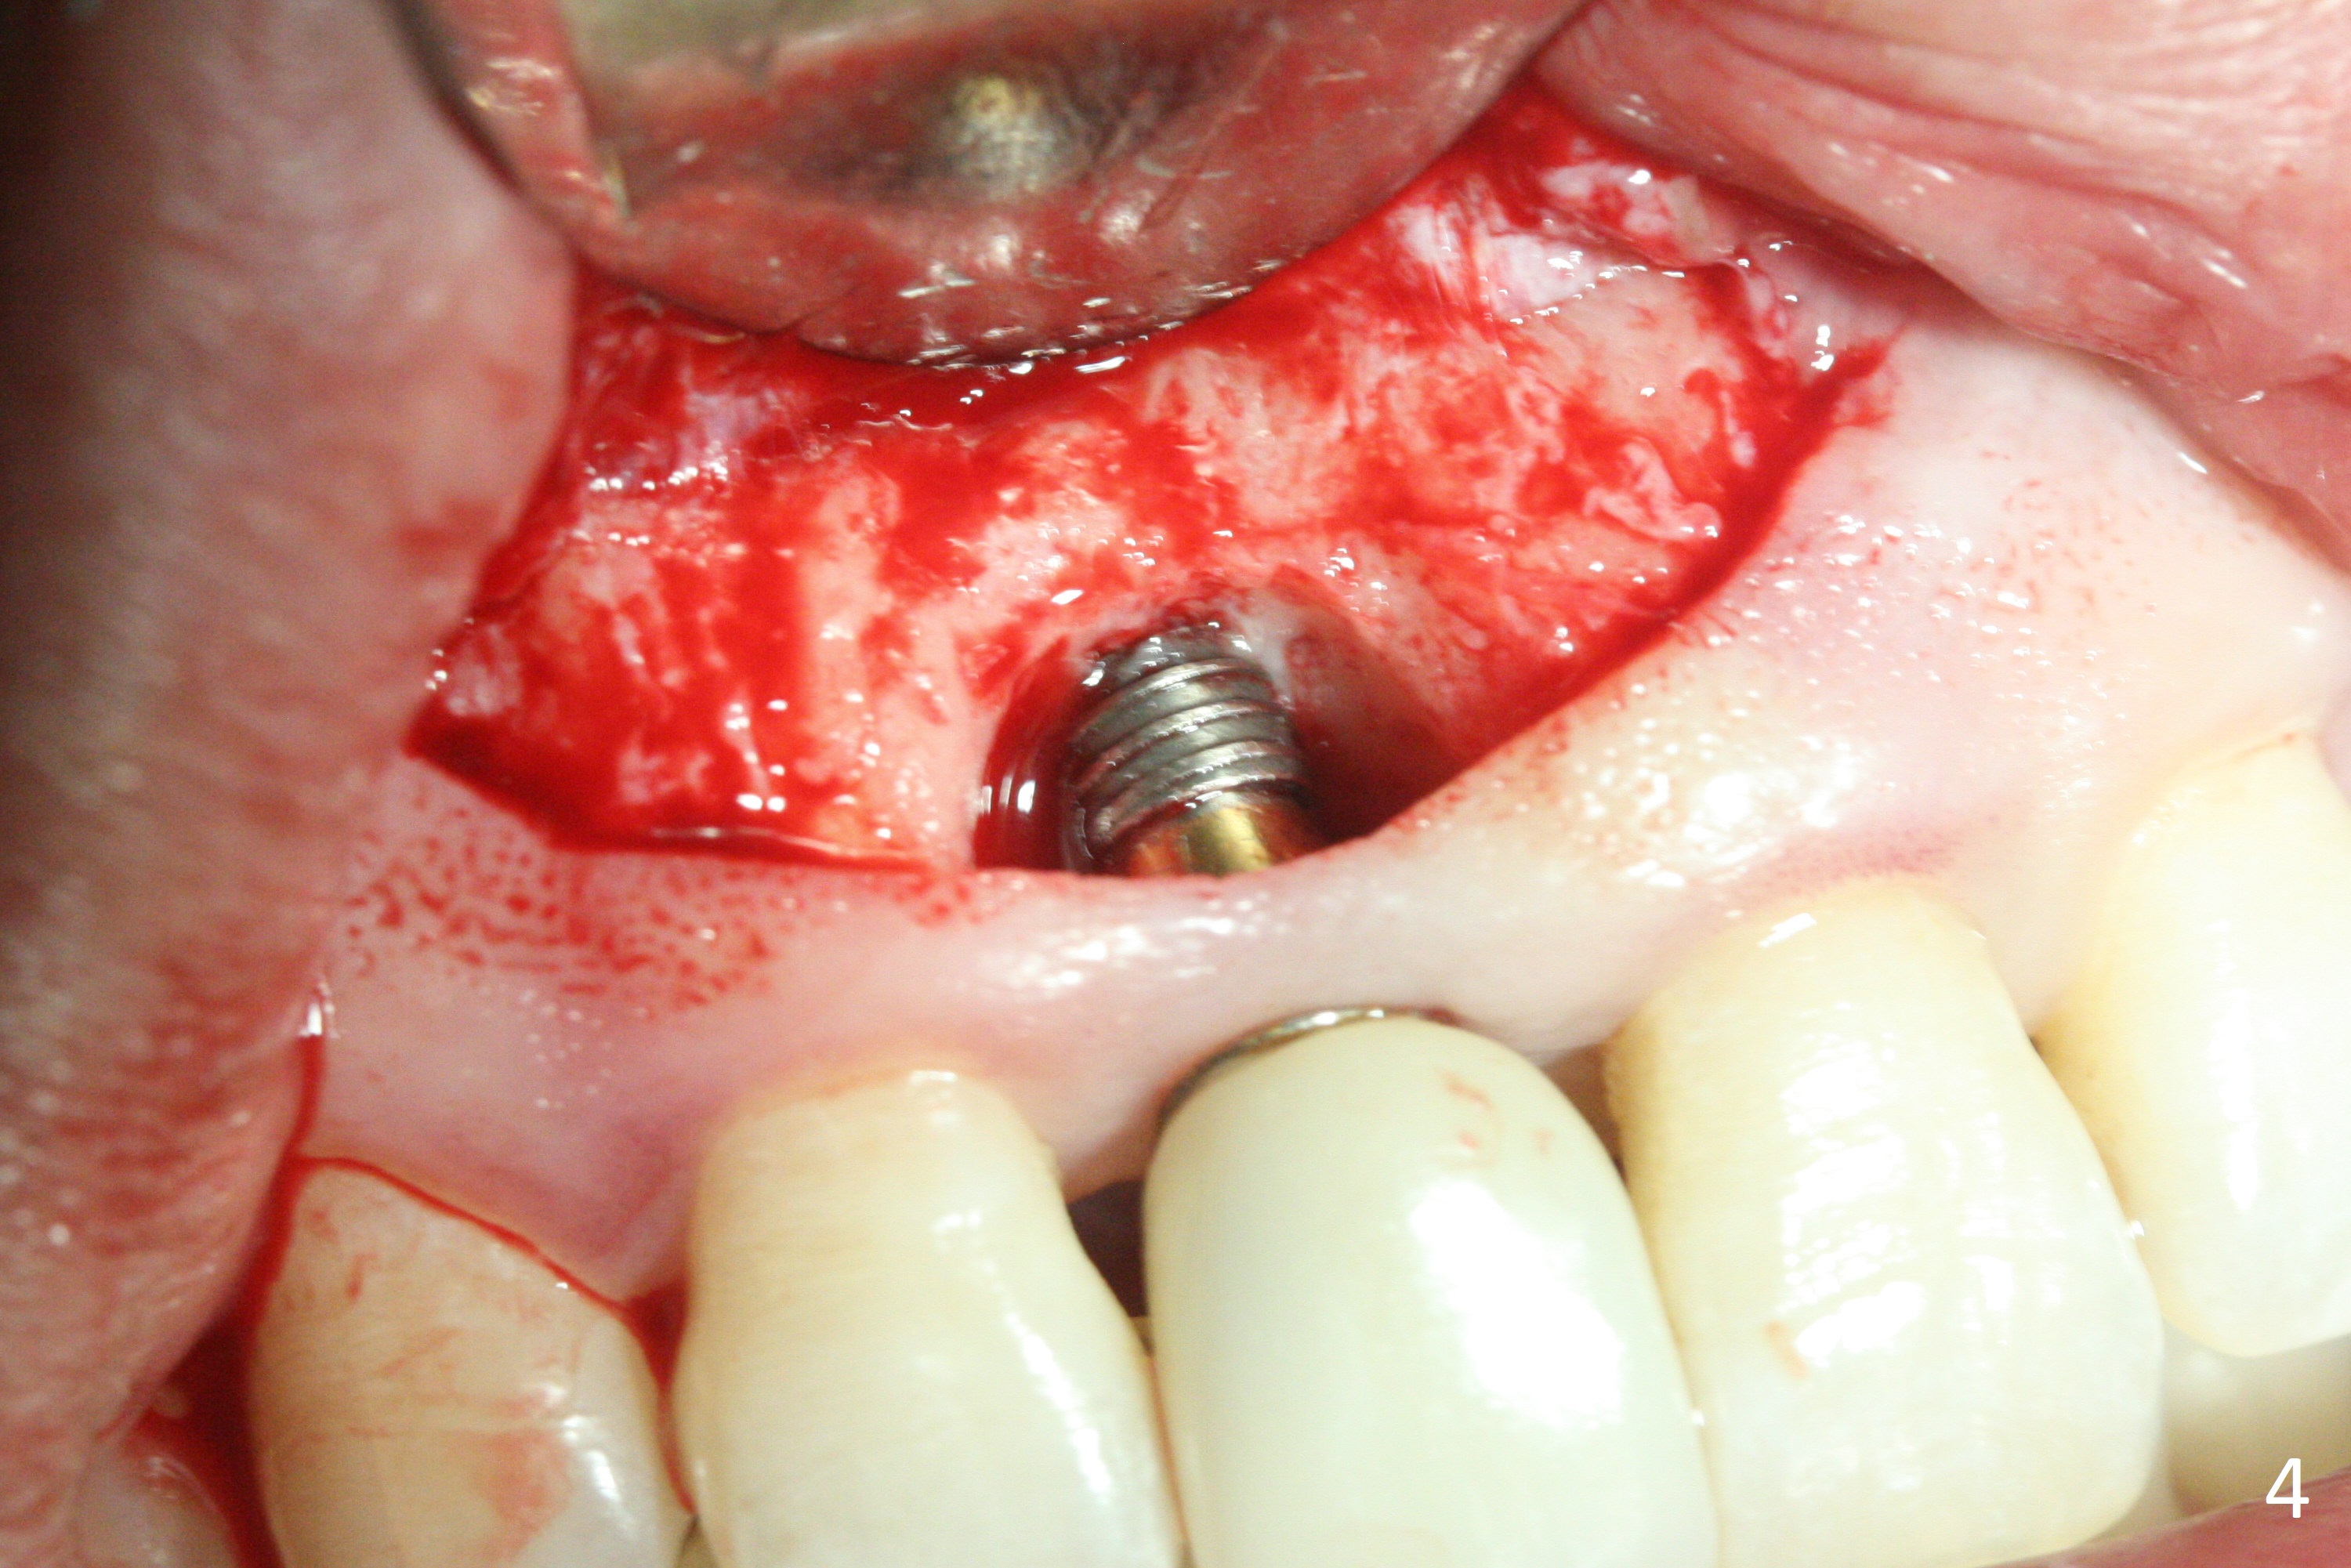

The patient returns because of purulent exudate from the buccal fistula (Fig.1 *) 1 year 9 months postop (1 year 3 months post cementation). Preop CT shows buccal thread exposure (Fig.2 arrowheads). To prevent postop gingival recession, a semilunar incision is made between the fistula and the gingival margin (Fig.3). After removal of granulation tissue (Fig.4), allograft in sticky bone form is packed (Fig.5). Following placement of PRF membrane and 6-month collagen membrane, the wound is closed (Fig.6). Since the implant (Fig.7 I) thread exposure is within bone (B) boundary (Fig.8 red dashed line), bone graft with PRF should be able to take care of periimplantitis (A: abutment). To prevent periimplantitis in similar situation, the immediate implant should be placed deep (not necessarily long, 18 mm) and narrower (3.5 mm instead of 3.8 mm). The defective buccal plate should be repaired with sticky bone and collagen membrane with incision if necessary. The wound does not dehisce 1 week postop (Fig.9) or 3 weeks postop (Fig.10, immediately post suture removal). Although bone graft seems to stay in place 6 months postop (Fig.11,12), the patient complains of bone graft expulsion sometimes. The buccal gingiva has deficiency (Fig.13). To fix it, make a remote incision (Fig.14 black line) and dissect before gingiva graft (Fig.15 dashed line). After removal of crown/abutment, the sinus track and implant surface are treated with Waterlase. A shorter cuff abutment is placed (4.5x5(4 to 3) mm) with a new provisional. The patient feels better with reduced sinus track 2 weeks postop (Fig.16).